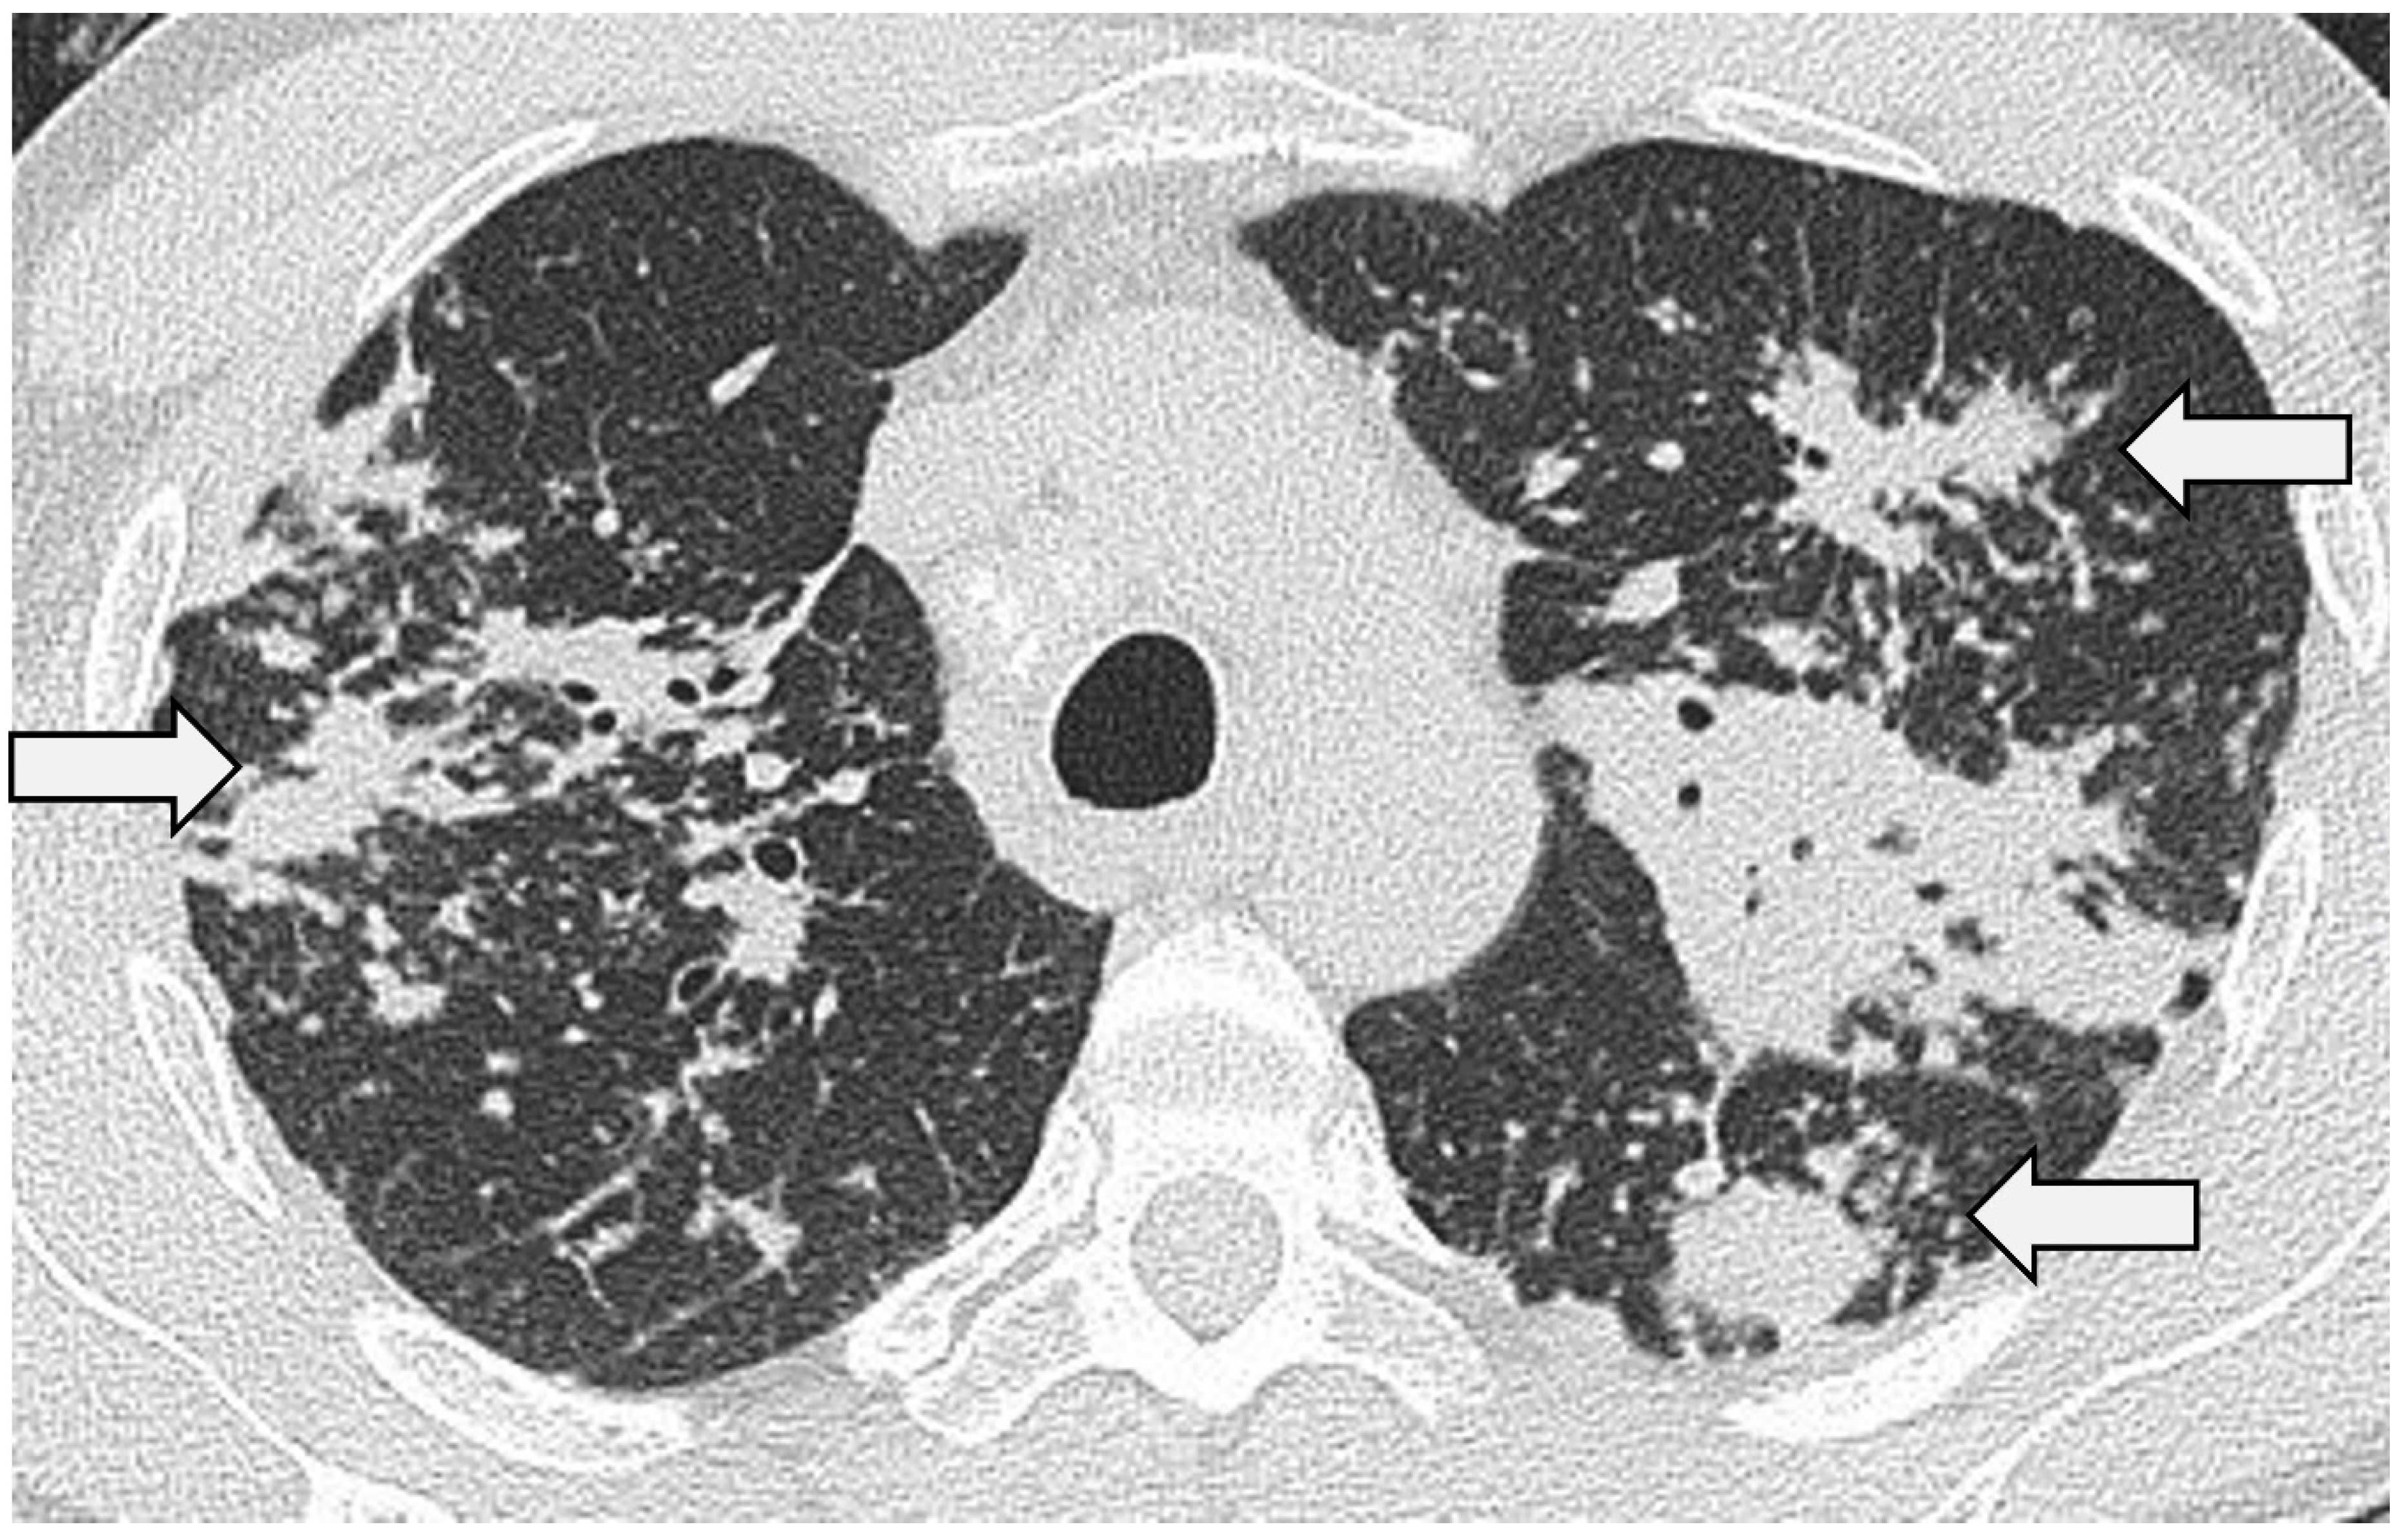

3.6. Pulmonary Fibrosis

Pulmonary fibrosis develops in 20–30% of patients [13,72]. The typical CT manifestations include coarse linear opacities, bronchocentric reticulation causing volume loss in the upper lobes and classical posterior retraction of the central bronchovascular structures [48,58] (Figure 6). Encasement of the bronchovascular bundles with conglomerate fibrosis masses may occur, with bronchial distortion and traction bronchiectasis/bronchiolectasis [10,47,73]. Honeycombing is seen in a significant minority and, in contrast to idiopathic pulmonary fibrosis (IPF), has a predilection for the mid-to-upper zones [10,74]. That said, in some patients, sarcoidosis does appear to masquerade as IPF on CT with basal predominant reticulation, ground-glass opacification and interlobular septal thickening [75]. In a recent study by Collins et al., 25 patients with combined sarcoidosis and IPF were reviewed [76]. Interestingly, the diagnosis of sarcoidosis was made, on average, a decade earlier than IPF; in 68%, sarcoidosis had been diagnosed on histopathologic examination at the time of IPF diagnosis. More importantly, survival in patients with combined disease was comparable to patients with classical IPF. Reports such as this raise the question of whether patients with combined disease represent a novel sarcoid phenotype or simply reflect a chance association (i.e., with IPF developing in patients with established sarcoidosis) [77].

Figure 6.

CT through the upper zones in a 61-year-old patient with pulmonary sarcoidosis. There is extensive disease with bronchocentric fibrosis manifest as a pattern of the consolidated lung. Note that in the left upper lobe, there is evidence of cavitation with a small aspergilloma (arrow).